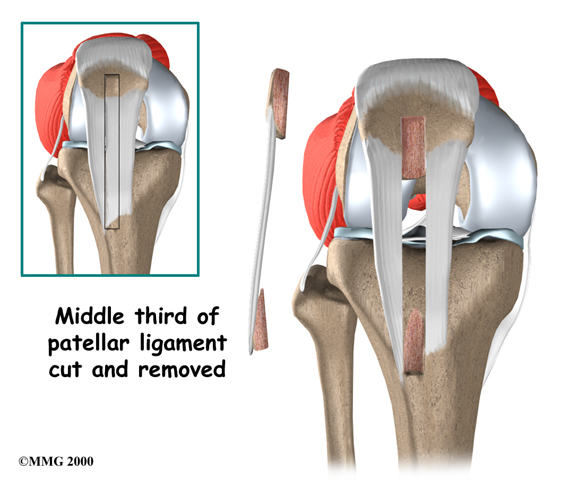

Patellar Tendon Graft

One type of graft used to replace the torn ACL is the patellar tendon. This tendon connects the kneecap (patella) to the tibia. The surgeon removes a strip from the center of the ligament to use as a replacement for the torn ACL.

Patellar Tendon